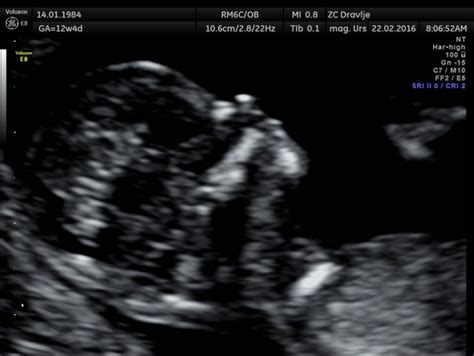

Ultrazvočni pregled za merjenje nuhalne svetline se običajno izvaja med 11. tednom nosečnosti (ko je dolžina ploda od temena do trtice med 45 in 84 mm) in 14. tednom nosečnosti. Sam pregled traja povprečno 15 minut. Pred naročanjem na pregled je priporočljivo, da nosečnica pozna prvi dan svoje zadnje menstruacije ali zaprosi svojega ginekologa za natančno izmerjeno velikost ploda od temena do trtice. Plodek namreč v tem obdobju povprečno zraste 2 mm na dan, kar omogoča natančnejše določanje optimalnega časa za pregled.

Pregled se začne z ugotavljanjem števila plodov in zaznavo plodovih utripov. Nato se izmeri natančna dolžina ploda od temena do trtice (crown-rump length - CRL), ki mora ustrezati obdobju med 11. in 14. tednom nosečnosti. Na podlagi te velikosti se določi predvideni dan poroda, ki ga kasneje v nosečnosti običajno ne spreminjajo več. Ugotovi se, ali se trajanje nosečnosti ujema z zadnjo menstruacijo, datumom prenosa zarodka pri postopku umetne oploditve ali pa bo predvideni dan poroda temelji na ultrazvočni meritvi plodove dolžine.

Po pregledu zgodnjega razvoja ploda sledi večkratno merjenje vratne svetline, ki ponazarja ultrazvočno temen prostor med kožo na plodovem vratu in mehkimi tkivi, ki prekrivajo hrbtenico. Vse meritve se slikovno zabeležijo. O največji zgornji normalni meji vratne svetline ne moremo govoriti, saj je ta odvisna od velikosti ploda. Vemo pa, da se verjetnost za srčno napako zelo poveča, ko meritev preseže 3,5 mm. Vedno je treba upoštevati tudi starost nosečnice ter morebitno prejšnjo nosečnost s kromosomsko nepravilno razvitim plodom.